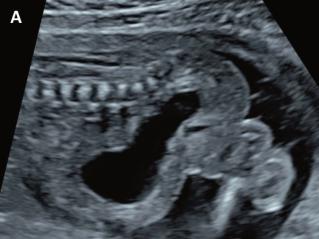

Zuweisung einer 29-jährigen Primigravida in der 17 4/7 Woche mit V.a. fetale Megazystis.

Was könnten die möglichen Ursachen für diese Problematik sein?